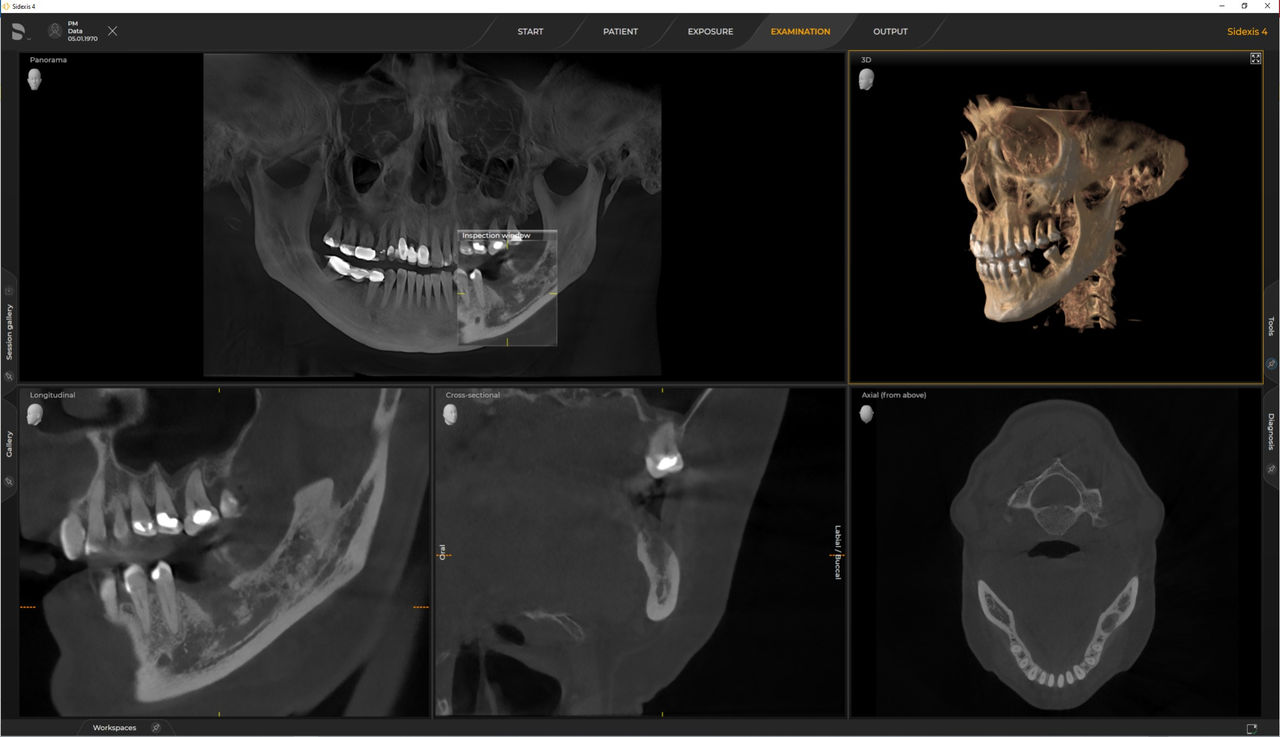

Las unidades 3D de Dentsply Sirona funcionan exclusivamente con Sidexis 4. Sin embargo, la migración de datos de Sidexis XG a Sidexis 4 es muy fácil. Sidexis 4 permite una experiencia digital completa con las últimas herramientas.